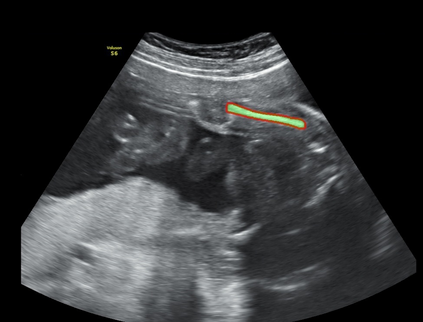

In this paper, we propose an end-to-end multi-task neural network called FetalNet with an attention mechanism and stacked module for spatio-temporal fetal ultrasound scan video analysis. Fetal biometric measurement is a standard examination during pregnancy used for the fetus growth monitoring and estimation of gestational age and fetal weight. The main goal in fetal ultrasound scan video analysis is to find proper standard planes to measure the fetal head, abdomen and femur. Due to natural high speckle noise and shadows in ultrasound data, medical expertise and sonographic experience are required to find the appropriate acquisition plane and perform accurate measurements of the fetus. In addition, existing computer-aided methods for fetal US biometric measurement address only one single image frame without considering temporal features. To address these shortcomings, we propose an end-to-end multi-task neural network for spatio-temporal ultrasound scan video analysis to simultaneously localize, classify and measure the fetal body parts. We propose a new encoder-decoder segmentation architecture that incorporates a classification branch. Additionally, we employ an attention mechanism with a stacked module to learn salient maps to suppress irrelevant US regions and efficient scan plane localization. We trained on the fetal ultrasound video comes from routine examinations of 700 different patients. Our method called FetalNet outperforms existing state-of-the-art methods in both classification and segmentation in fetal ultrasound video recordings.